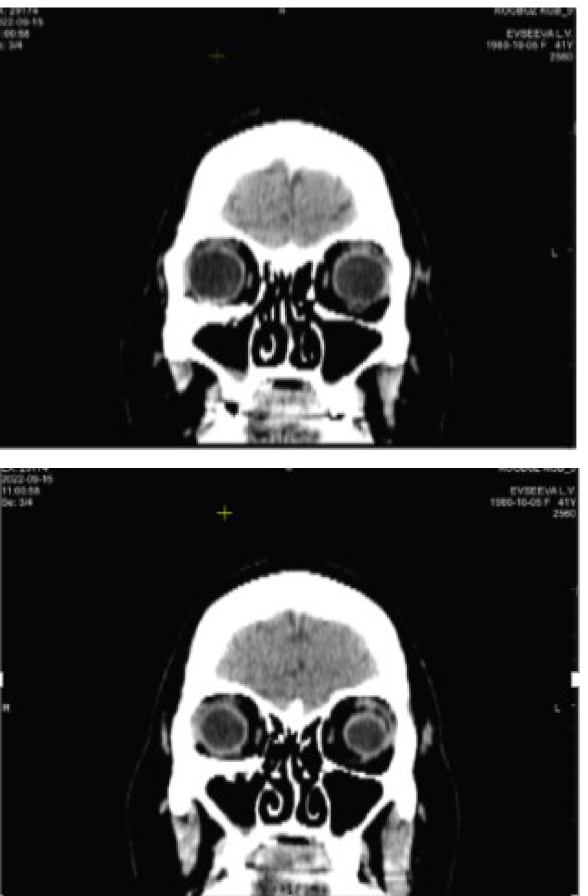

Клинический пример 1. Родители пациентки С. 10 лет обратились с жалобами на ограничение подвижности левого глаза вверх и двоение. Из анамнеза известно, что неделю назад девочка ударилась головой при падении. По данным компьютерной томографии (КТ), слева имеется трещина нижней стенки орбиты в средней трети шириной 2 мм. В зоне локализации перелома – дефект нижней прямой мышцы, предположительно разрыв, пролапс мягких тканей орбиты в верхне-челюстную пазуху до 9 мм. При объективном осмотре в первой позиции взора выявлена ортотропия и полное отсутствие подвижности левого глаза кверху (рис. 1). Пациентке поставлен диагноз: перелом нижней стенки орбиты, разрыв нижней прямой мышцы. Рекомендована ревизия зоны перелома и нижней прямой мышцы cito.

По данным КТ: фиброзное утолщение нижней прямой мышцы слева, пластинка выполняет контур нижней стенки глазницы (рис. 4).

Рис. 4. Компьютерная томография орбит через год после операции. Клинический пример 1